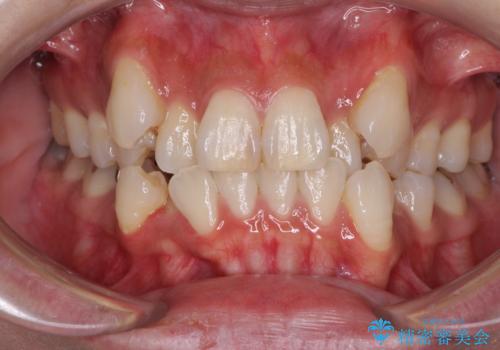

- 八重歯や前歯のデコボコを気にして来院された患者様です。

目立たない装置を希望されたので、上顎が裏側装置のハーフリンガルを選択し、上下左右の小臼歯(計4歯)を抜歯して矯正治療を行うこととしました。